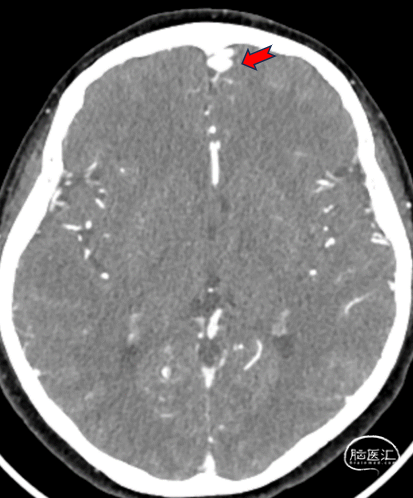

术前头颅CTA:红色箭头可见粗大引流静脉,前颅底DAVF可能。

➢术前影像学检查:CTA及MRA提示左侧前颅底硬脑膜动静脉瘘(DAVF)。

➢初步诊断:左侧前颅底DAVF。